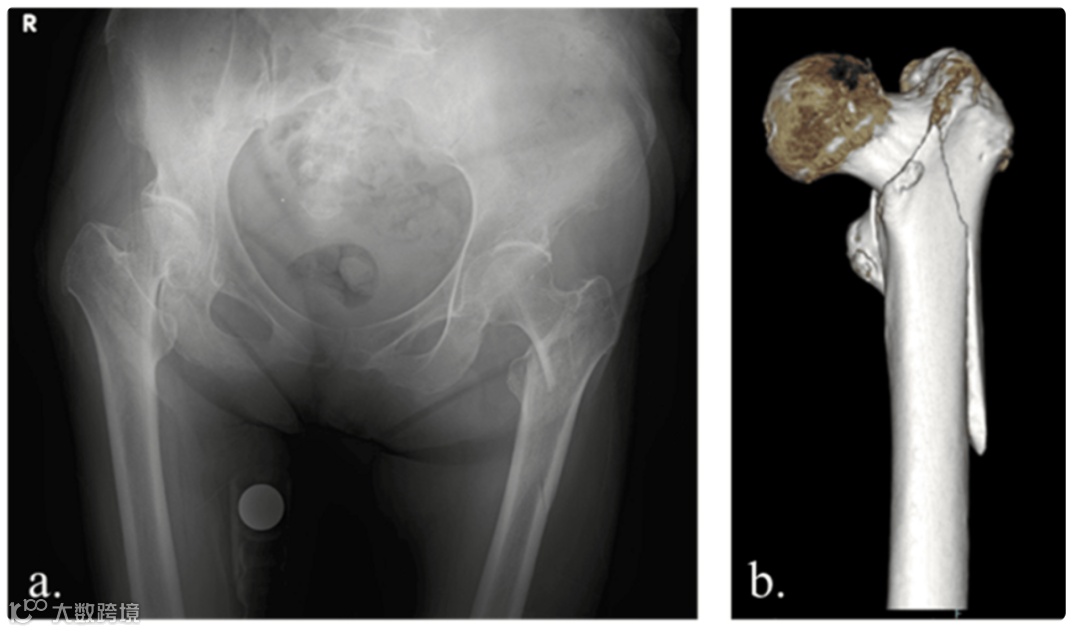

图2. 术后X线片

术前X线片和三维计算断层扫描图像未提示转移性骨肿瘤,左髋部可见近端股骨骨折(图1)。手术在牵引床上仰卧位进行,手术时间89分钟,估计失血量110 ml。手术使用了IPT-EF钉,并采用NESPLON缆索系统进行转子下固定(图2)。术后次日,患者开始负重并进行步态训练。